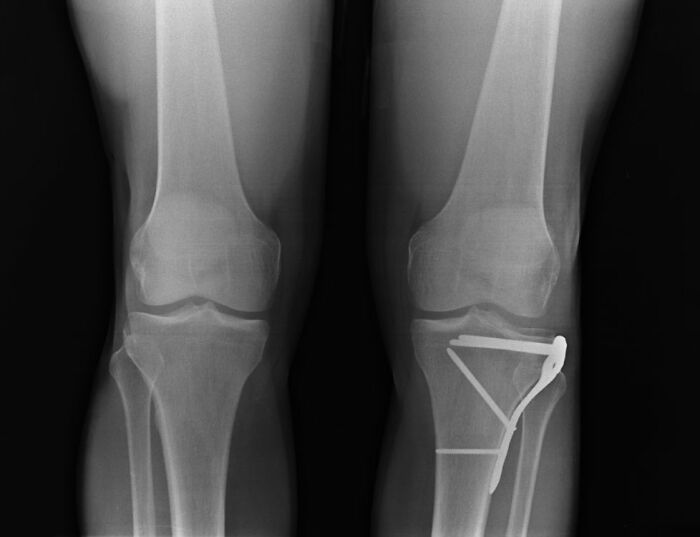

#6 Why Would Urgent Care Need To Bother With An X-Ray Anyway...?

I work in EMS. We got a call for a female with leg pain. When we arrive on scene, this woman’s leg is three times the size of her other one, blue and purple, and she has no pulse in her foot. She fell on ice a few days prior and the urgent care didn’t do any X-rays, told her she had a sprain and gave her a walking boot. In reality, her tibia and fibula were both so badly fractured they were cutting the blood vessels and muscle tissue. She lost her foot.